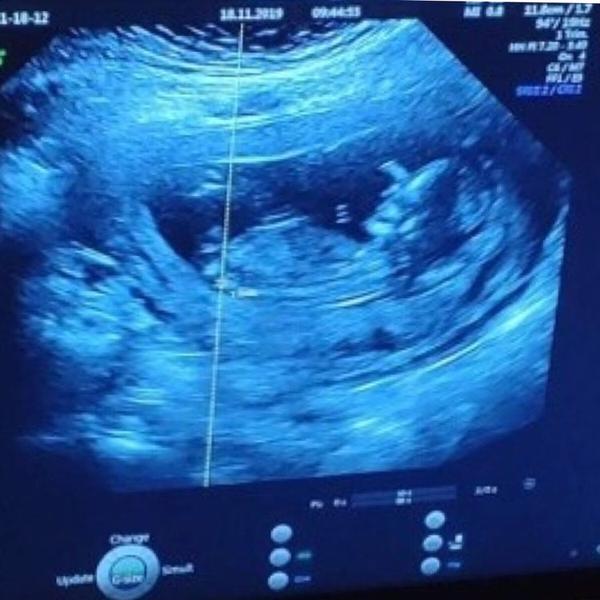

Ahojky holky, tak včera po měsíci kontrola a screening...

V čekárně čekání 40min , ta nervozita atd.

Krev, moč vše ok, ultrazvuk už přes břicho.

Hned se mimi ukázalo, mávlo ručkou a šup a otočilo se na bok a nene neotočím se.

Tak mudr trošku třepal s bříškem.

Vše nos ruky nohy kosti organy v pořádku.

Riziko dow.syndromu 1:8555

Prý chcete vědět pohlavi?

Ano chceme

Tak holčička a termín 28.5.2020